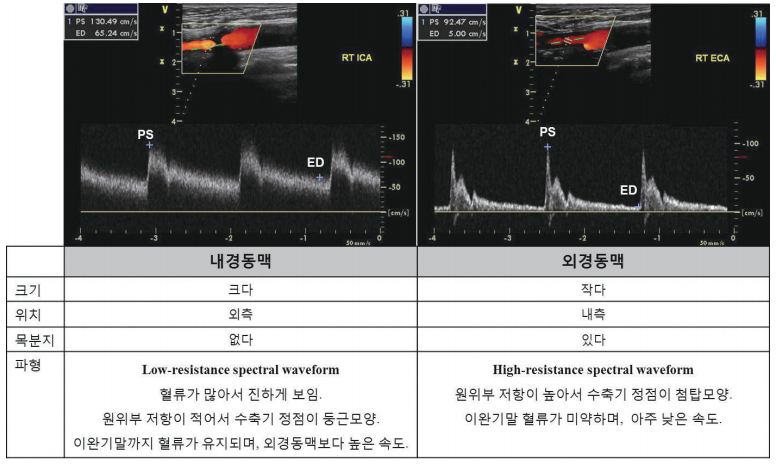

경동맥은 목에서 얼굴로 올라가면서 외경동맥과 내경동맥으로 나뉘는데, 내경동맥은 안구에 혈액을 공급하므로 내경동맥이 좁아지거나 막히면 시력이 나빠집니다. 또한 내경동맥이든 외경동맥이든 굵은 부위가 막힐수록 손상을 받는 부위는 넓어집니다. 많은 경우 증상 없이 지내기도 하지만 일시적으로 뇌로 가는 피의 공급이 차단되어 중풍과 비슷한 증상을 일시적으로 느끼는 경우도 있습니다.

경동맥 협착증은 경동맥 초음파로 간단히 진단할 수 있는데, 컴퓨터 단층촬영(CT), 경동맥 도플러 검사, 자기공명촬영(MRI)을 이용한 경동맥 조영술을 통하면 경동맥 협착증의 정도를 정확히 확인할 수 있습니다. 이를 통해 예방 차원에서 경동맥 확장술을 시행하여 뇌경색의 위험을 예방할 수 있습니다.